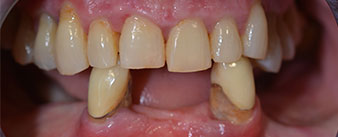

Die 64-jährige Patientin wurde mit einer Unterkiefer-Restbezahnung 38, 33 und 43 und einer klammerbefestigten Interimsprothese im Unterkiefer vorstellig (Abb. 1 und 2).

Unterkiefer-Restbezahnung

Abb. 1

Abb. 2

Die notwendige parodontologische Behandlung und Extraktion im Oberkiefer sollte zu einem späteren Zeitpunkt erfolgen, da die Patientin Lehrerin ist und zu dem Zeitpunkt mit Abiturprüfungen beschäftigt war. Sie konnte weder essen noch adäquat sprechen, da die Interimsprothese sehr häufig und bei der kleinsten Belastung brach.